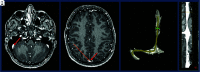

Background and purpose: Dural venous sinus stenosis has been associated with idiopathic intracranial hypertension and isolated venous pulsatile tinnitus. However, the utility of characterizing stenosis as intrinsic or extrinsic remains indeterminate. The aim of this retrospective study was to review preprocedural imaging of patients with symptomatic idiopathic intracranial hypertension and pulsatile tinnitus, classify the stenosis, and assess a trend between stenosis type and clinical presentation while reviewing the frequencies of other frequently seen imaging findings in these conditions.

Materials and methods: MRVs of 115 patients with idiopathic intracranial hypertension and 43 patients with pulsatile tinnitus before venous sinus stent placement were reviewed. Parameters recorded included the following: intrinsic or extrinsic stenosis, prominent emissary veins, optic nerve tortuosity, cephalocele, sella appearance, poststenotic fusiform enlargement versus saccular venous aneurysm, and internal jugular bulb diverticula. χ2 cross-tabulation statistics were calculated and recorded for all data.

Results: Most patients with idiopathic intracranial hypertension (75 of 115 sinuses, 65%) had extrinsic stenosis, and most patients with pulsatile tinnitus (37 of 45 sinuses, 82%) had intrinsic stenosis. Marked optic nerve tortuosity was more common in idiopathic intracranial hypertension. Cephaloceles were rare in both cohorts, with an increased trend toward the presence in idiopathic intracranial hypertension. Empty sellas were more common in idiopathic intracranial hypertension. Cerebellar tonsils were similarly located at the foramen magnum level in both cohorts. Saccular venous aneurysms were more common in pulsatile tinnitus. Internal jugular bulb diverticula were similarly common in both cohorts.

Conclusions: In this cohort, most patients with idiopathic intracranial hypertension had extrinsic stenosis, and most patients with pulsatile tinnitus had intrinsic stenosis. Awareness and reporting of these subtypes may reduce the underrecognition of potential contributory stenoses in a given patient's idiopathic intracranial hypertension or pulsatile tinnitus.